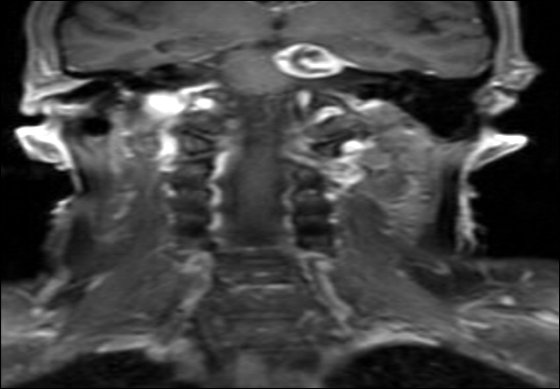

Brain Tumour Causing Left Sided Facial Pain

Brain Tumour Causing Facial Pain

Brain Tumour Causing Pain